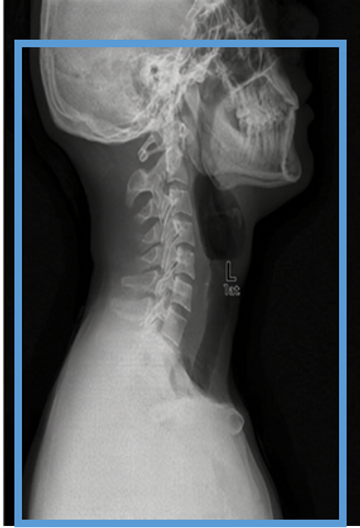

As a general rule, scan field should be from Carina to Sella turcica when patient is positioned properly. Be aware of diagnosis to ensure that all relevant anatomy is included. If patient is unable to position properly and a large portion of brain/skull will need to be scanned please clear with radiologist to ensure that no additional orders will need to be obtained

SCAN FROM AORTIC ARCH TO SELLA TURCI

125 ml omnipaque 350 injected at 4cc/second. Bolus track on the Aortic Arch at 80 HU.